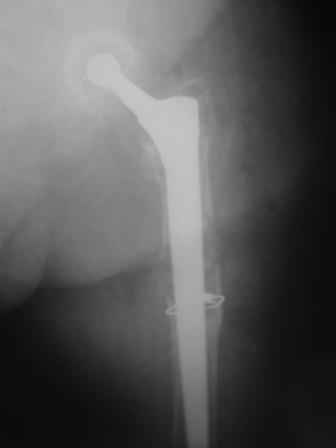

You transformed a cemented hip prosthesis to a cementless revision hip prosthesis with a little approach.

* your nail has a point of minus resistance at the tip of femural stem and at the fulcrum of the fracture; by the time could it break?

* by the time stem and nail could reciprocally move?

* distal fixation of the nail is based near only on two screws : are they sufficient to secure a good stability before fracture consolidation?

The nail tip is jammed. Since it is conical, it can only be jammed more with axial load.

I'd say yes because we use same 6 mm screws for femoral nailing and allow immediate weight-bearing regardless of fracture pattern.